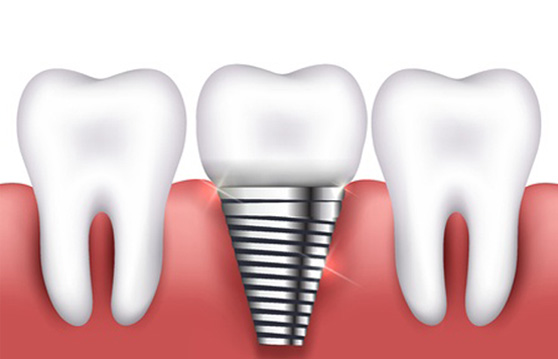

ÀÓÇöõÆ® ¼ö¼ú Àü CTÃÔ¿µÀ» ÅëÇØ ÀÕ¸ö»ÀÀÇ Á¤È®ÇÑ ¸ð¾ç°ú Å©±â µîÀ» ÀÔüÀûÀ¸·Î ÀçÇöÇÏ¿© ½Ä¸³ À§Ä¡¸¦ °áÁ¤ÇÕ´Ï´Ù.